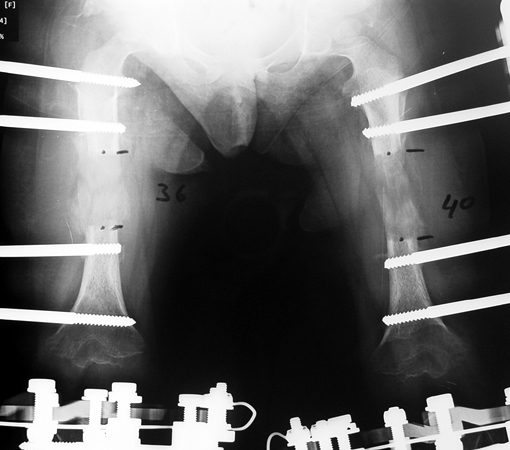

14 ve 16 yaşlar arasında her iki femurda toplam 10-12 cm boy uzatma her iki kalçanın fleksiyon deformitesinin düzeltilmesi (bu lomber hiperlordozu düzeltir) her iki kalçanın varus deformitesini düzeltme ortalama eksternal fiksasyon tedavi süresi = 10-12 ay

12-14 yaşları arasında Her iki tibiada toplam 10-15cm boy uzatma (iki seviyeli uzatma) Proksimal tibianın varus deformitesini proksimal osteotomi ile düzeltilmesi Distal tibianın varus deformitesi distal osteotomi ile düzeltmesi Distal tibianın varus deformitesi distal osteotomi ile düzeltmesi Boy uzatmanın sonunda lateral kollateral ligamentin gerilmesi Ortalama eksternal fiksasyon tedavi süresi = 8-10 ay

Vaka 3